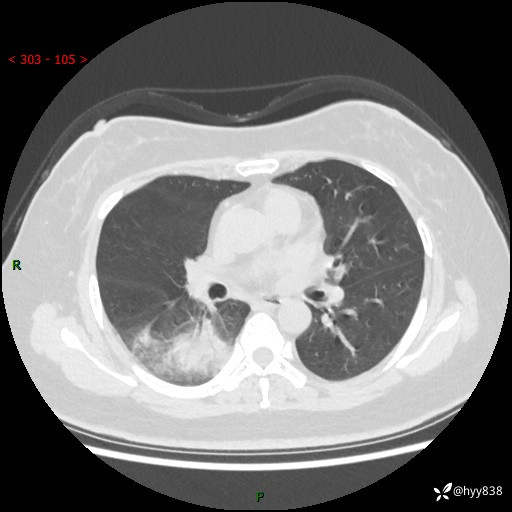

大叶性肺炎的表现形式,晒晒鉴别诊断吧…结果公布~

主诉:间断咳嗽、咳痰8天

简要病史:患者8天前无明显诱因出现咳嗽、咳痰,为绿色脓痰,无明显加重与缓解因素,无高热、寒战,无呼吸困难,无大量脓痰,无哮鸣音,于当地医院行胸片示右下肺团块影,性质待定,予口服药物治疗症状未见明显改善,具体药名不详,为求进一步诊治来我院就诊,门诊以“肺占位性病变”收入我科进一步诊治。 患者自发病以来,精神、饮食尚可,睡眠欠佳,大小便正常,体力、体重未见明显异常。

辅助检查:CT

临床诊断:肺占位

胸部CT平扫